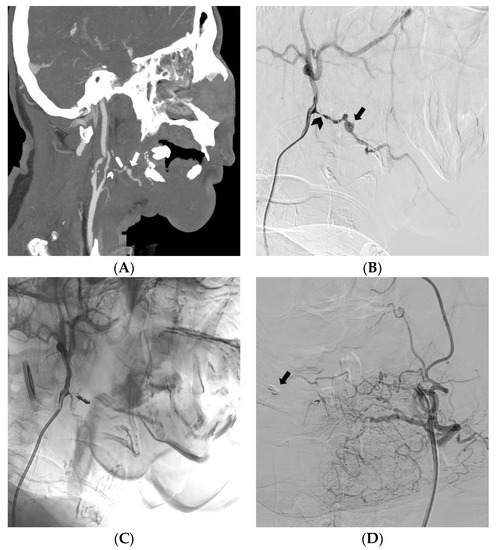

| Site of bleeding - Pelvic - Upper GI - Lower GI - Abdomen - Thorax - Neck - Limbs | 15 (28.4%) 4 (7.5%) 2 (3.8%) 18 (34%) 8 (15%) 2 (3.8%) 4 (7.5%) |

| Cause of bleeding - Trauma - Spontaneous - Others (tumors, diverticula, ulcers, etc.) | 31 (58.5%) 5 (9.4%) 16 (32.1%) |